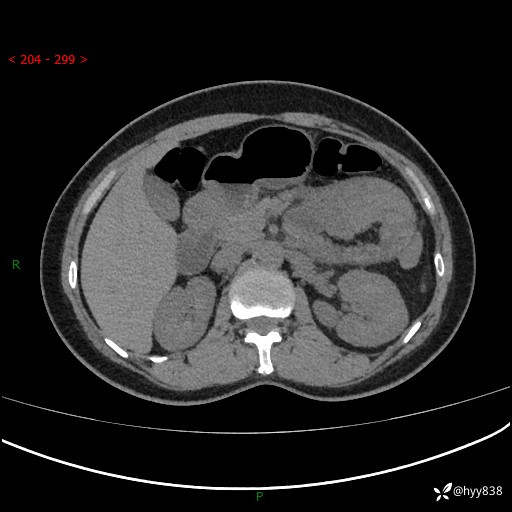

现病史:患者1天前无明显诱因下出现左上腹部及腰背部胀痛不适,阵发性加剧,伴肛门停止排气;无发热,无恶心呕吐,无畏寒发热,无心慌气短等不适,于当地市第二人民医院就诊,行腹部ct检查提示左上腹区肠系膜血管从剧聚集,分布紊乱伴肠管局限性稍扩张积液,不完全性肠梗阻;考虑子宫颈纳氏囊肿,双侧附件区囊状灶;予以抗炎及对症支持等治疗后未见明显缓解,现患者为求进一步治疗来我院急诊就诊,遂以“肠梗阻”收住入院。 病来,神志清,精神可,饮食睡眠不佳,经灌肠后排便2次,小便正常,体力体重无明显变化。

上腹部CT平扫